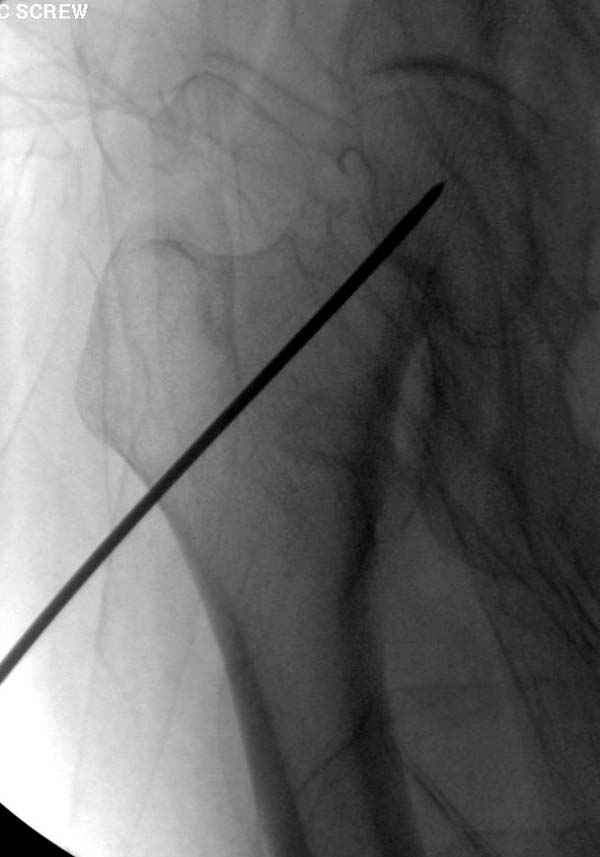

Профилактику дальнейшего раскола неполного перелома шейки провели тремя канюлированными шурупами.

вопрос вне контекста: при введении каннюлированных

винтов как часто пользуетесь гайдом? и пользуетесь ли вы им всегда?

Я имел ввиду параллельный направитель,

обеспечивающий параллельное расположение винтов. к

Наверное речь идет насчет parallel guide из набора. Применяем по возможности всегда, но,

как видно на снимке, не всегда получается

паралельно.

Такие несмещенные переломы обычно для молодых резидентов, и бывают технические неточности, но в этом случае посчитали фиксацию адекватной.

Соблюдая правила, многократными попытками можно

увеличить риск стрессового перелома латерального

кортекса.